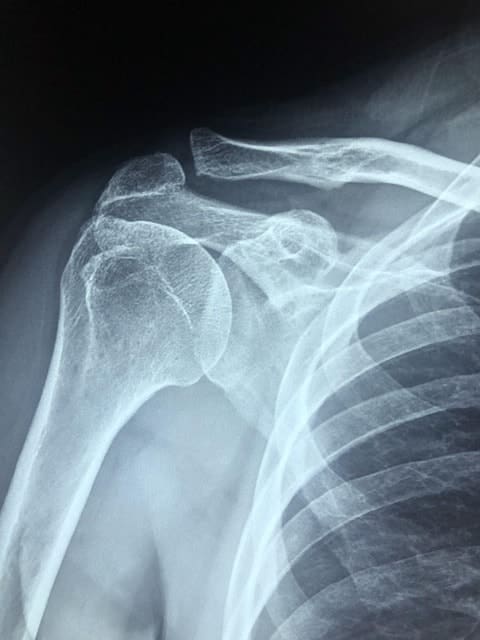

Torn Rotator Cuff

Rotator cuff tears can result from a specific injury or develop gradually over time through repetitive motions. The severity of the injury depends on how many shoulder tendons are torn or damaged. Common symptoms include pain, weakness, limited mobility, and clicking or popping sensations when moving the arm.

Workers’ compensation covers all reasonable and necessary medical expenses. Medical treatment is covered as long as your physician deems it necessary. If physical therapy and non-invasive treatment don’t successfully address your shoulder injury, your physician may refer you for arthroscopic shoulder surgery, where a camera and surgical instruments are inserted through a small incision.

Arthroscopic shoulder surgery settlements may be worth more than a settlement for an injury successfully treated with non-invasive methods. Other shoulder surgeries are more invasive and typically result in a higher settlement value.

More severe or permanent injuries typically have larger settlement amounts. A left rotator cuff injury or a right biceps tear may also be higher if it is the injured worker’s dominant arm. Partial tears that can be treated with physical therapy will likely have a lower settlement value than an injury to the shoulder joint that requires corrective surgery.